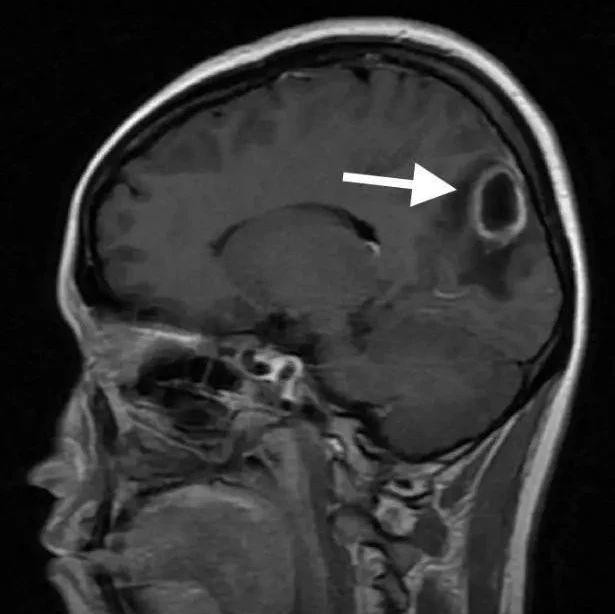

77岁免疫健全男性,表现为进行性头痛和意识模糊。MRI可见大量脓肿。脑脊液化验提示白细胞计数为1250个/mm3(中性粒细胞占65%),微生物培养阴性。二次脑活检,行通用PCR提示为梭杆菌属。最终诊断:脑脓肿。

影像挑战:老年男性,进行性头痛和意识模糊(结果公布)